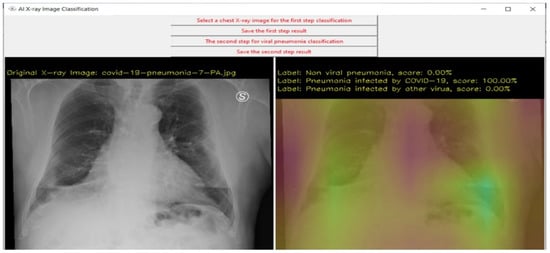

8. Case Study